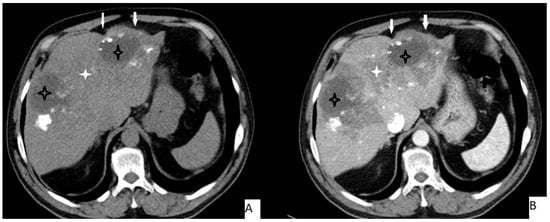

The most frequently encountered CT pattern was a heterogeneous mass with calcifications and hypoattenuating areas (72.3%). Most of the lesions had irregular contours (85.4%), 85.4% lacked contrast enhancement, 77.4% of the lesions had calcifications, and atrophy and capsular retraction was present in 10.7% of the lesions (Figure 2 and Figure 3). Table 3 details the distribution of CT appearances.

Figure 2.

51-year-old male. Hepatic lesion with irregular contours and calcifications on precontrast axial CT (A). On portal venous images (B), no enhancement is present in the lesion. Central necrosis can be seen (A,B—black star). Perilesional enhancement (B—white star) and capsular (A,B—arrows) retraction are present.

Figure 3.

53-year-old female. Hepatic lesion with irregular borders and calcification (A,B—arrows) on precontrast axial CT (A). On portal venous images (B), no enhancement is present in the lesion. Central necrosis can be seen (B—black star). Perilesional enhancement (B—white star) is present.